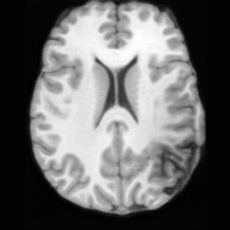

(a)PathologicalInput ImageSynthSR [18]Brain-ID [28]UNA [30]USBHealthyGround TruthRefer to captionRefer to captionRefer to captionRefer to captionRefer to captionRefer to captionRefer to captionRefer to captionRefer to captionRefer to captionRefer to captionRefer to captionRefer to captionRefer to captionRefer to captionRefer to captionRefer to captionRefer to captionRefer to captionRefer to captionRefer to captionRefer to captionRefer to captionRefer to caption(b)HealthyInput ImageConditionalLesion MaskUNA [30]USBRefer to captionRefer to captionRefer to captionRefer to captionRefer to captionRefer to captionRefer to captionRefer to captionRefer to captionRefer to captionRefer to captionRefer to captionRefer to captionRefer to captionRefer to captionRefer to caption

Figure 5: Comparison of bidirectional brain editing. (a) pathology-to-healthy, the circles and arrows highlight lesion regions and unsuccessful reconstructions; (b) healthy-to-pathology. Note that SynthSR and Brain-ID cannot perform healthy-to-pathology editing.

Pathology-to-Healthy Editing. Fig. 5 (a) presents comparison results on four input brain images with lesions of varying sizes, shapes, and densities. All competing models, although specialized for healthy brain image synthesis, struggle to reconstruct pathological regions, especially near lesion boundaries. In contrast, USB accurately reconstructs the corresponding healthy brain, even in challenging cases with large, high-density lesions where normal brain structures are almost completely obscured (last row). Tab. 2 provides a quantitative comparison for pathology-to-healthy editing, where USB achieves the best performance across all three datasets, demonstrating the effectiveness of its unified framework in reconstructing healthy brains from pathological inputs. Additional results are in Suppl. B.